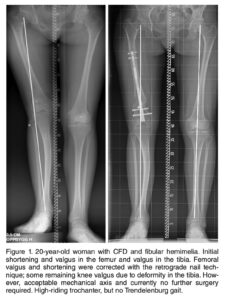

Sob a coordenação do Dr. Marcelo Pigatto D’Amado, membro da Sociedade Brasileira de Ortopedia e Traumatologia e da AO Foundation, o CBOT é pioneiro no uso de hastes intramedulares motorizadas (PRECICE, FITBONE) para alongamento ósseo no Brasil.